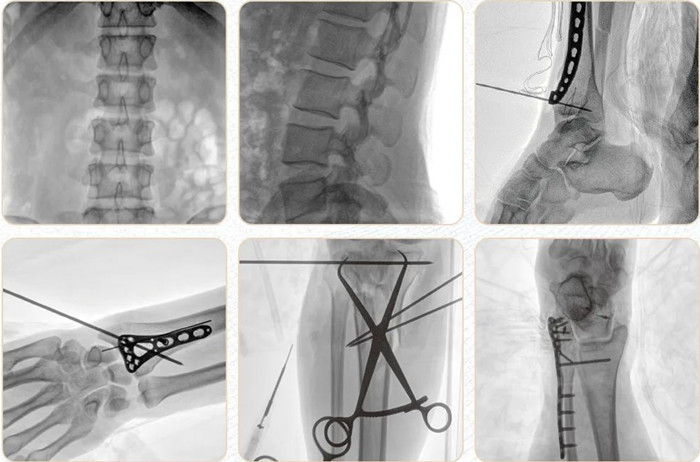

移動式平板C形臂PLX118F-Plus臨床應(yīng)用范圍:可應(yīng)用在骨科、普通外科、矯形外科、創(chuàng)傷外科、泌尿外科、脊柱外科、疼痛外科、消化科、腫瘤科、婦產(chǎn)科等科室。